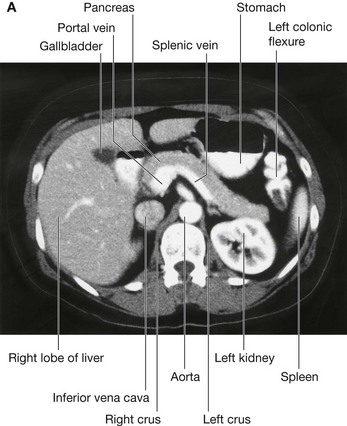

Vertebral level LI

The transpyloric plane is a horizontal plane that transects the body through the lower aspect of vertebra LI (Fig. 4.16). It:

image is about midway between the jugular notch and the pubic symphysis, and crosses the costal margin on each side at roughly the ninth costal cartilage;

image crosses through the opening of the stomach into the duodenum (the pyloric orifice), which is just to the right of the body of LI; the duodenum then makes a characteristic C-shaped loop on the posterior abdominal wall and crosses the midline to open into the jejunum just to the left of the body of vertebra LII, whereas the head of the pancreas is enclosed by the loop of the duodenum, and the body of the pancreas extends across the midline to the left;

image crosses through the body of the pancreas; and

image approximates the position of the hila of the kidneys; though because the left kidney is slightly higher than the right, the transpyloric plane crosses through the inferior aspect of the left hilum and the superior part of the right hilum.

The gastrointestinal system and its derivatives are supplied by three major arteries

Three large unpaired arteries branch from the anterior surface of the abdominal aorta to supply the abdominal part of the gastrointestinal tract and all of the structures (liver, pancreas, and gallbladder) to which this part of the gut gives rise to during development (Fig. 4.17). These arteries pass through derivatives of the dorsal and ventral mesenteries to reach the target viscera. These vessels therefore also supply structures such as the spleen and lymph nodes that develop in the mesenteries. These three arteries are:

image the celiac artery, which branches from the abdominal aorta at the upper border of vertebra LI and supplies the foregut;

image the superior mesenteric artery, which arises from the abdominal aorta at the lower border of vertebra LI and supplies the midgut; and

image the inferior mesenteric artery, which branches from the abdominal aorta at approximately vertebral level LIII and supplies the hindgut.